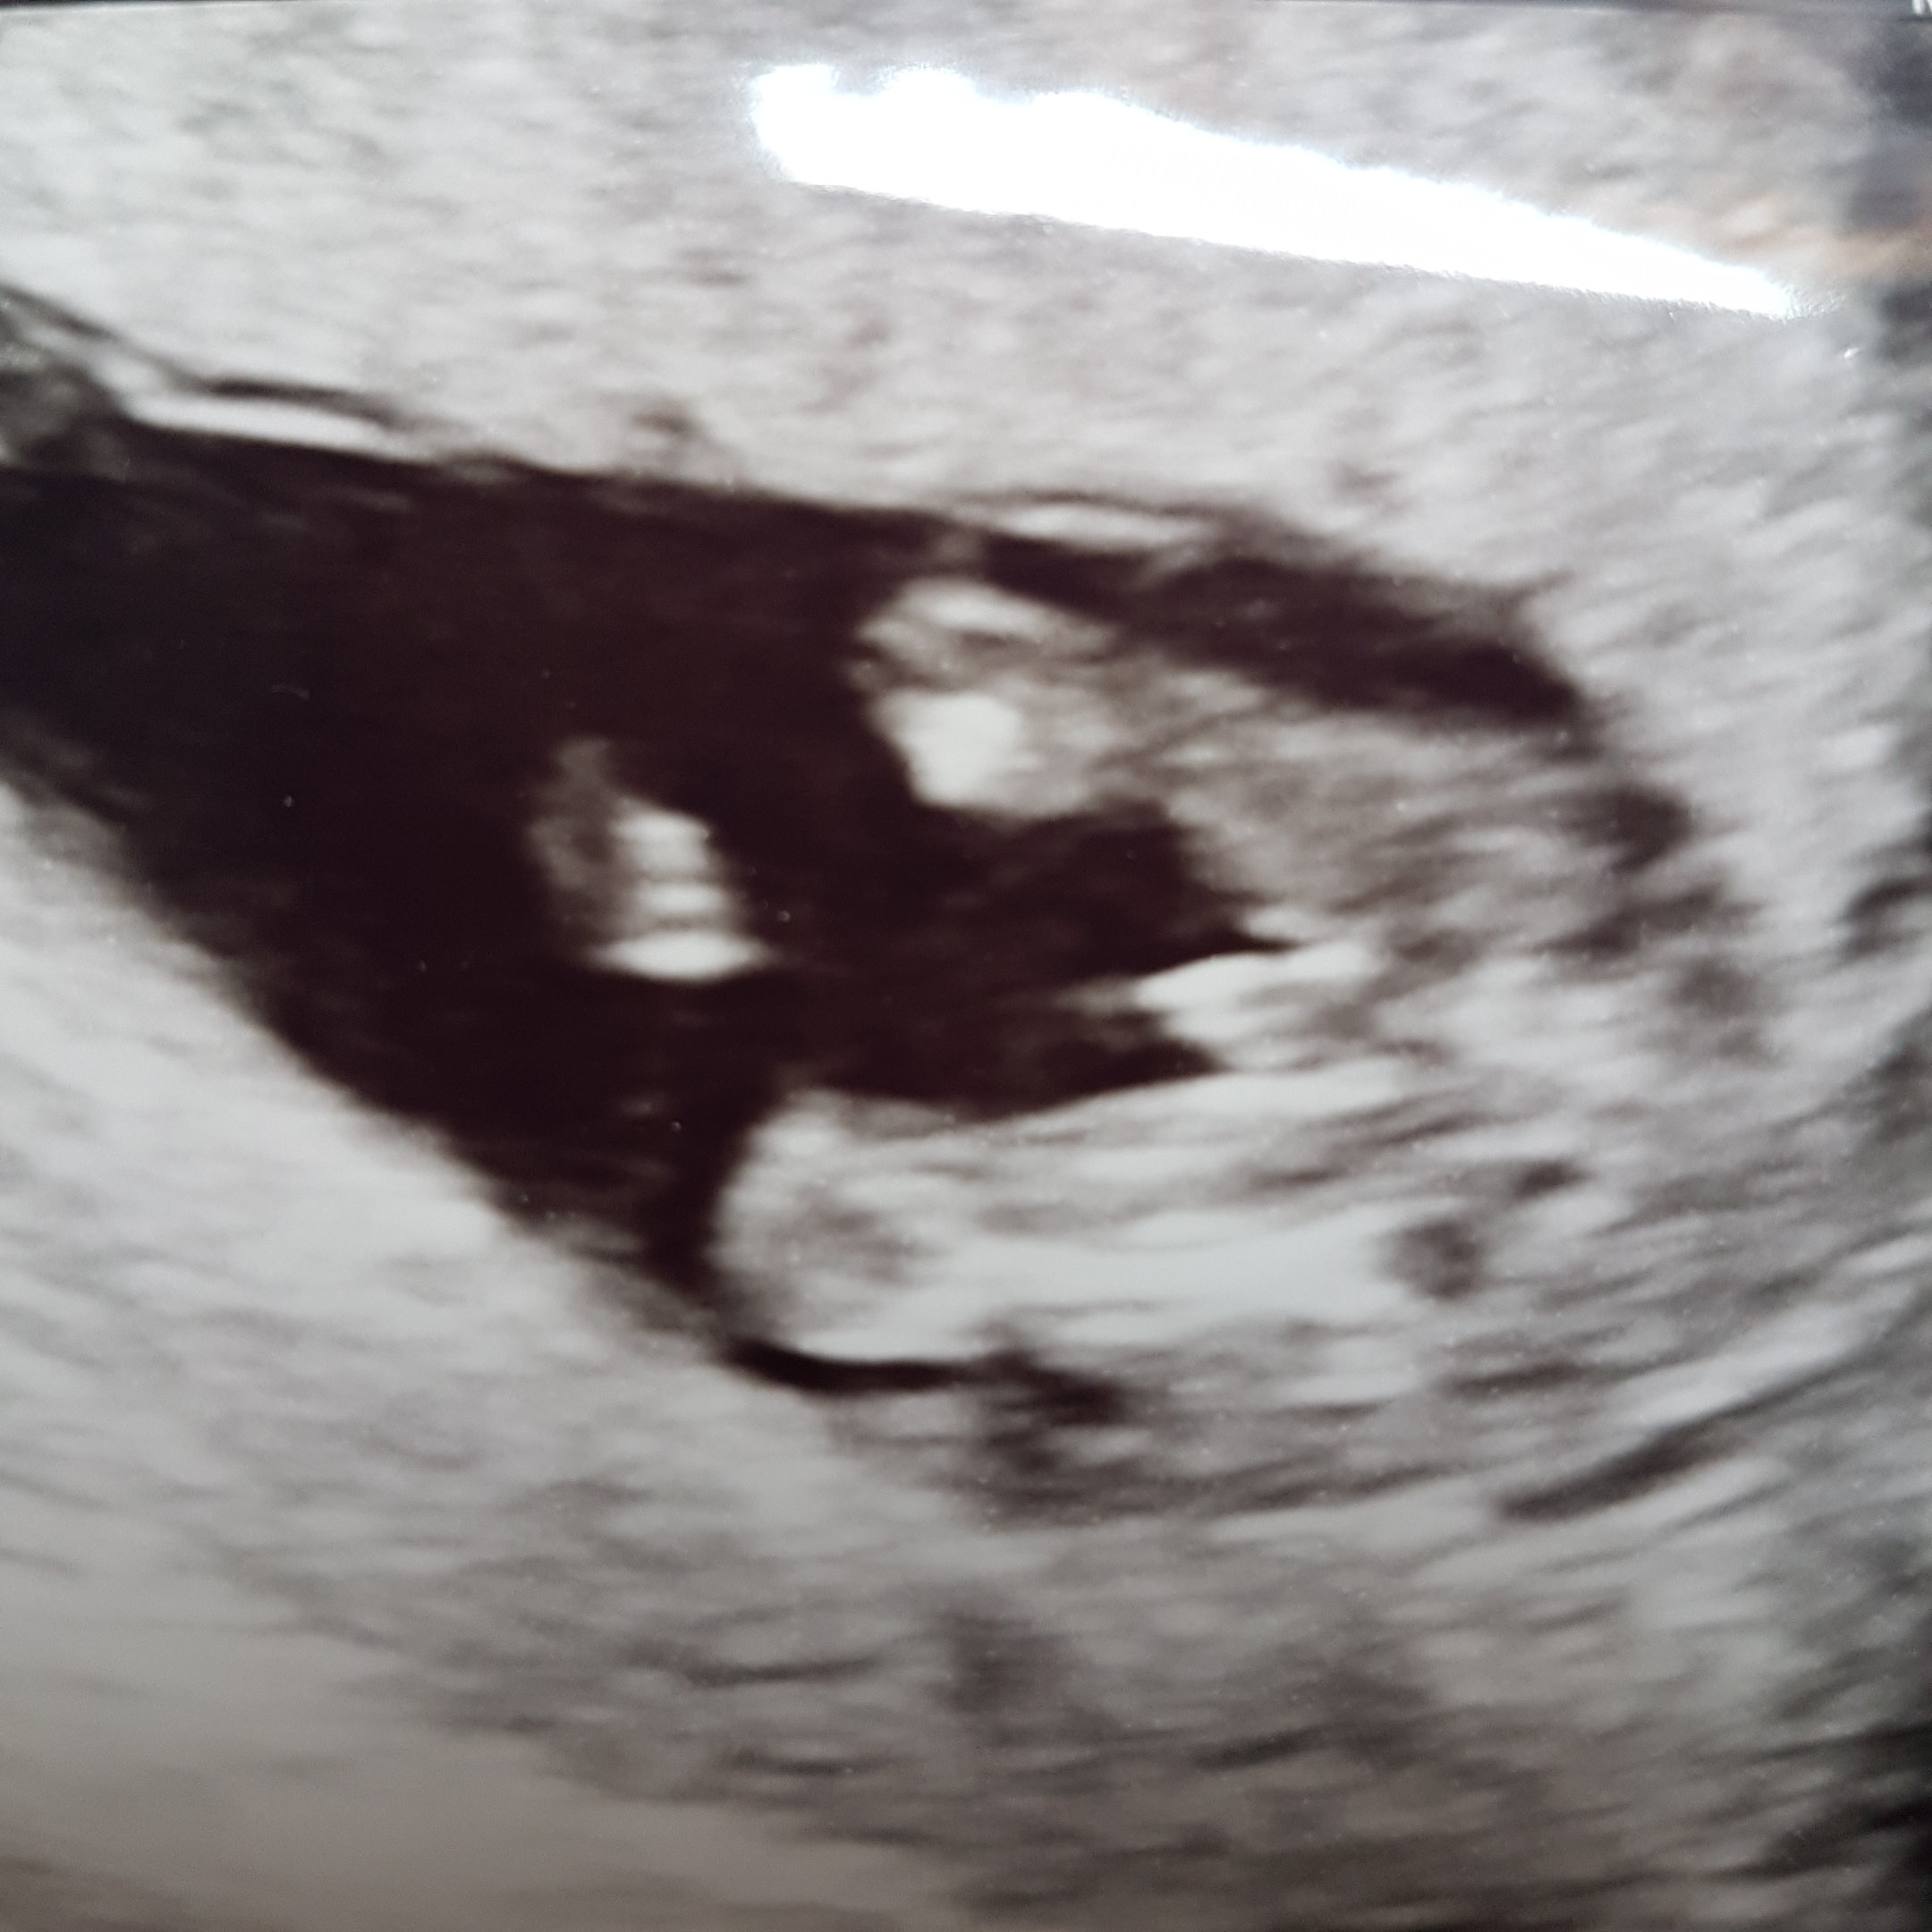

Kochane tak na szybko wpadam. Jestem po wizycie. Maleństwo zdrowe. Waży 91g cm ile to niewiem bo się krecilo. Dzisiaj 14t1d poznałam płeć. Będę mieć Syna. Marzył mi się drugi syn.

20170613_124730.jpg

Lecę teraz do dentysty bo mam termin. Odezwę się później i wstawię resztę zdjęć